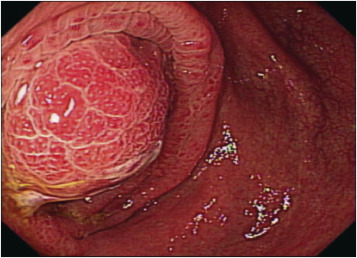

A 67-year-old man came to the outpatient department with intermittent right lower abdominal pain ongoing for 1 month. He denied any systemic disease and had no fever, chills, hematochezia, chronic diarrhea, nor body weight loss. Physical examination revealed right lower quadrant tenderness without rebound pain and muscle guarding. Positive psoas sign was noted. Blood tests were unremarkable except mild elevated C-reactive protein (4.9 mg/dL). Abdominal computed tomography (CT) demonstrated marked appendiceal wall swelling and intraluminal filling defect of contrast medium over the appendix (Figure 1). The colonoscopy revealed a protruding mass with edematous mucosa at cecum (Figure 2). Biopsy obtained at colonoscopy revealed inflammation of appendix mucosa. Due to the cancer could not be ruled out, a surgery with right hemicolectomy was performed and which showed a 7-cm length appendiceal tumor (Figure 3). Hematoxylin and eosin staining showed irregular glands with stromal invasion to muscularis propria, intraluminal mucin extravasation, and abscess formation were also seen (Figure 4A). Glandular arrangement lining by pseudostratified columnar cells with enlarged vesicular nuclei was noted under high magnification (Figure 4B). On the basis of these findings, he was diagnosed as colonic type adenocarcinoma of the appendix, T2N0M0, Stage I. After right hemicolectomy, he remains asymptomatic to date.

Figure 1. Computed tomography images: (A) cross section of abdominal computed tomography showed an appendiceal tumor (white arrow); and (B) marked appendiceal wall swelling and intraluminal filling defect of contrast medium over appendix noted (white arrow). |